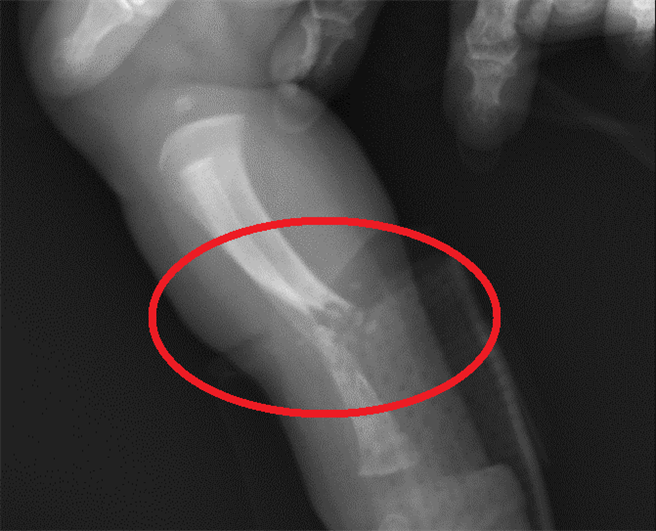

一名由外院轉至中國醫藥大學兒童醫院僅一天大的女嬰右小腿骨折,經檢查其發現鈣、磷、鎂、副甲狀腺、肝腎功能皆正常,但是維他命D嚴重缺乏,新生兒科主任林鴻志診斷為「新生兒佝僂病」,這也是他從醫30年首次遇到不足月的嬰兒就患有佝僂病而骨折,經進一步檢查也發現其母親的維他命D也嚴重缺乏。

林鴻志表示,女嬰一出生就右小腿腫脹,觸摸時會嚎哭,從外院轉至該院經檢查發現右小腿骨折,是極度和長期缺乏維生素D造成新生兒佝僂病,懷疑是在母親妊娠晚期胎兒骨骼礦物質的沉積中斷造成其骨骼軟化和弱化,加上產程擠壓造成骨折,足月新生兒的佝僂病通常是因為母親的維他命D缺乏所造成。

該名嬰兒經檢查其發現鈣、磷、鎂、副甲狀腺、肝腎功能皆正常,但是維他命D嚴重缺乏,其維生素D僅有7ng/ml,正常值為30以上,該女嬰除會診骨科在骨折處上石膏固定,並給予口服維生素D治療,林鴻志說,補充維他命D平均3-6個月,一旦補充到正常值,就不用擔心日常生活會有佝僂病症狀。

他解釋,新生兒佝僂病於嬰幼兒期可能出現呼吸困難、骨折、驚厥、活動受限、畸形癒合、發育遲緩等,將影響一生的骨骼健康,目前可透過檢驗血中的鈣、磷、鹼性磷酸(Alkaline Phosphatase)以及超音波、X光影像來診斷。